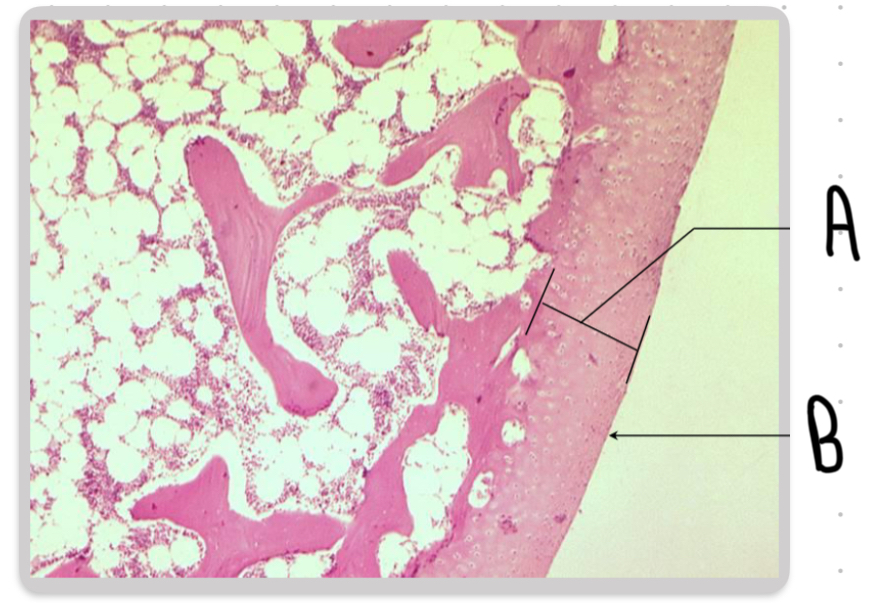

What are the structures labeled A in this image?

Trabeculae.

What are the structures labeled B in this image?

Osteoblasts.